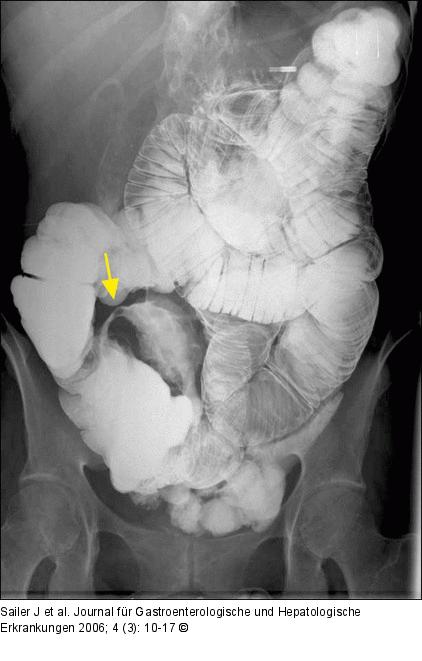

Abbildung 1b: Enteroklysma Konventionelles Enteroklysma bei fortgeschrittenem Morbus Crohn mit "Pflasterstein-Relief" im terminalen Ileum und kurzstreckig mäßiggradiger Stenose valvulär (Pfeil). |

Konventionelles Enteroklysma bei fortgeschrittenem Morbus Crohn mit "Pflasterstein-Relief" im terminalen Ileum und kurzstreckig mäßiggradiger Stenose valvulär (Pfeil). |